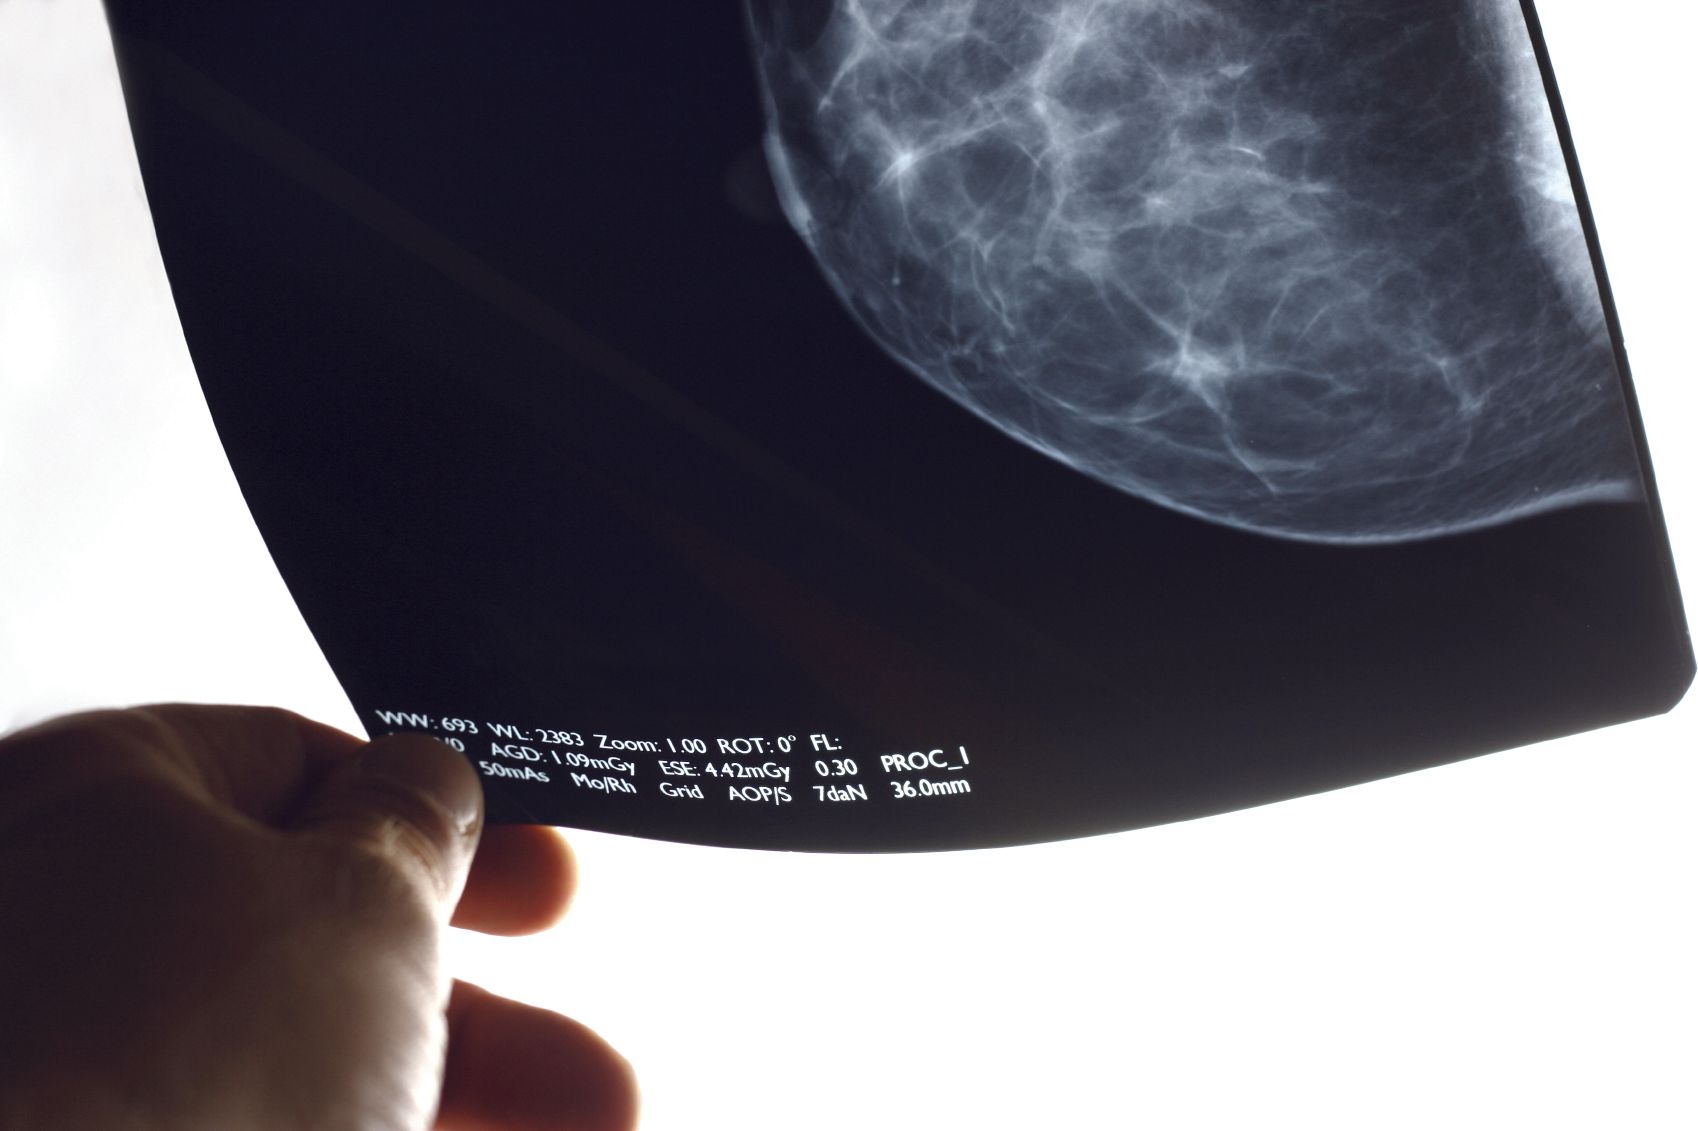

A clinical investigation published in Radiology: Artificial Intelligence demonstrated that the concurrent use of a new artificial intelligence (AI) tool improved the diagnostic performance of radiologists in the detection of breast cancer by mammography without prolonging their workflow.1

Researchers used MammoScreen, an AI tool designed to identify regions suspicious for breast cancer on 2D digital mammograms and determine their likelihood of malignancy. The system produces a set of image positions with scores for suspicion of malignancy that are extracted from the 4 views of a standard mammogram.

In this multireader, multicase retrospective study, a dataset including 240 digital mammography images were analyzed by 14 radiologists by a counterbalance design, where each half of the dataset was read either with or without AI in the first session and vice versa for a second session, with the 2 sessions separated by a washout period. End points assessed by the investigators included area under the receiver operating characteristic curve (area under the curve [AUC]), sensitivity, specificity, and reading time.